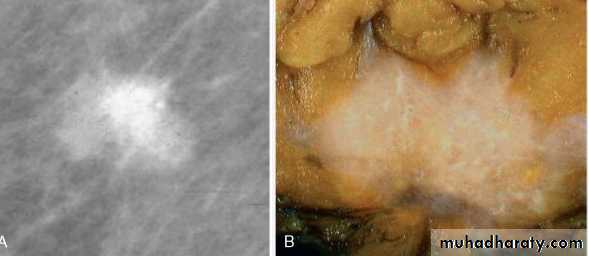

mammography, invasive carcinomas most commonly present as a radiodense mass

most common in women in the sixth decade and presents as a well-circumscribed mass. It may closely mimic a benign lesion clinically and radiologically, or present as a rapidly growing mass.tumor is soft, fleshy (medulla is Latin for “marrow”), and well circumscribed.